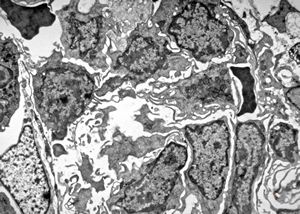

M,58y. | spleen - thesaurismosis of unknown origin … postmedicamentous?

M,44y. | spleen - Gaucher disease